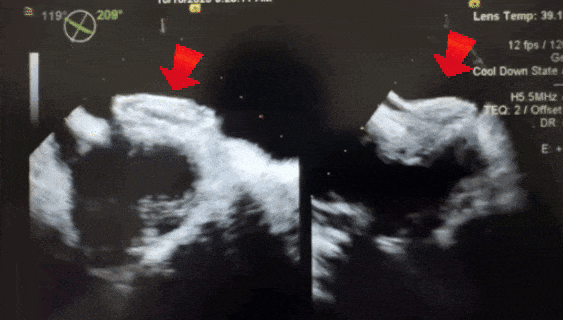

释放后超声

释放封堵器后,封堵器盘面稳固贴壁,成型良好,超声下未见分流,封堵成功。

四腔心切面下观察封堵器,左右盘面稳固贴壁,盘面平整,未影响瓣膜结构

主动脉短轴切面下观察封堵器,封堵器形态稳定,无残余分流

术前经超声检查确诊为16mm房缺,合并有12mm的大范围软缘,术中复测显示剑下双房心切面缺损大小为14.5mm,软缘范围11.7mm,结合术前与术中测量大小,选择BDASD-Ⅰ30可降解房间隔缺损封堵器。对于此类伴有较大软缘的房缺,术中超声精确评估缺损大小、软缘范围及边缘条件,是确保封堵器成型良好、稳定锚定与手术成功的关键。术中左右盘面展开顺利,锁定后牵拉稳定,封堵器位置良好。术后超声确认封堵器盘面平整,呈现完美的三明治形状,且无残余分流。可降解房缺封堵器拥有降落伞成型锁定结构,即使伞盘较大也能保证盘面的稳定性,稳定夹持大范围软缘。术后给予阿司匹林抗血小板治疗,预防血栓形成。